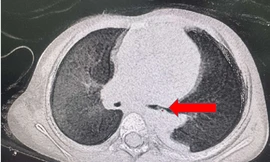

TPO - Ngày 26/12, thông tin từ khoa Hô Hấp 1 - BV Nhi Đồng 2 cho biết đơn vị này vừa tiếp nhận bé trai N.N.Đ.K , 5 tuổi, ngụ ở Đồng Nai, với tình trạng viêm xẹp thùy trên phổi trái. Tại đây, các bác sĩ phát hiện có dị vật nằm trong phổi suốt 2 năm, là một mảnh xương gà.